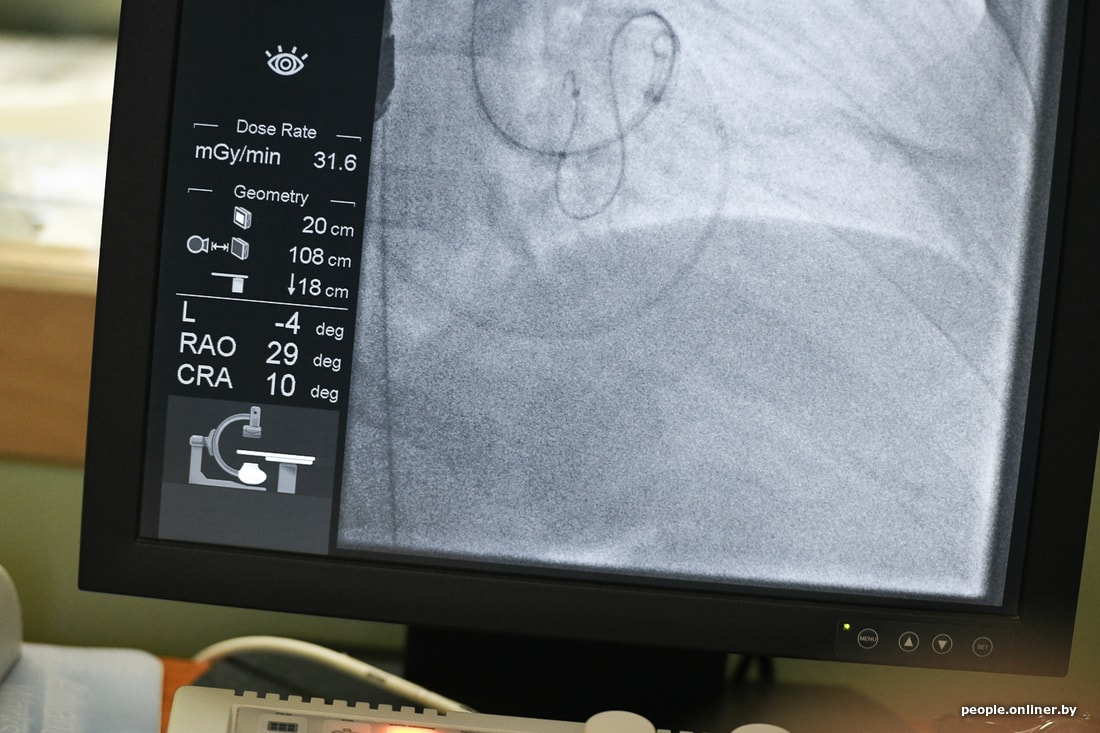

Это не просто прогрессивная методика, она очень интересная, если можно сказать, остроумная. Калифорнийские специалисты создали устройство, которое позволяет уменьшить раздутый желудочек сердца изнутри. Устройство заводится внутрь полости сердца, и в стенку сердца изнутри вводятся якоря, соединенные ниткой, шнуром. Стягиваются. Тем самым раздутый желудочек уменьшается, принимает свой оптимальный размер, начинает лучше работать. Потому что чем желудочек больше, тем сложнее ему сокращаться по физическим законам. Я ввожу катетеры через бедренную артерию под контролем рентгена и ультразвука. Техника заключается в том, чтобы через артерии довести устройство до сердца и расположить внутри именно там, где нужно. Тут уже работает команда: и кардиологи, и ультразвуковые диагносты, и мы, рентгеноэндоваскулярные хирурги.